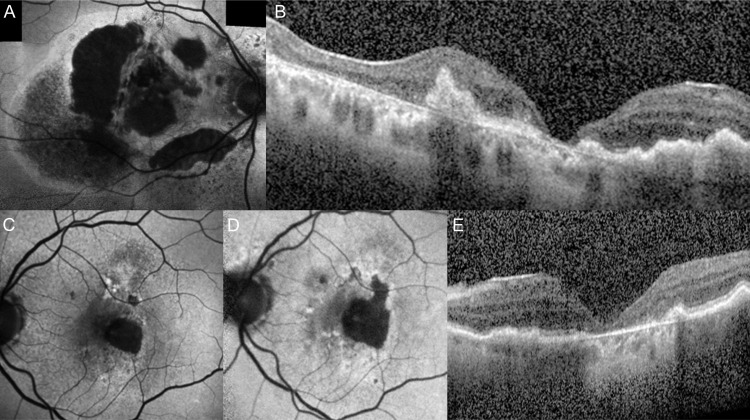

地理萎缩(GA)是一种晚期老年性黄斑变性(AMD),影响美国约100万人,全球约500万人。在这篇综述中,视网膜成像技术用于诊断和监测AMD中GA的进展,以及与GA发生和进展相关的危险因素。为了使临床医生熟悉GA患者的常见表型,强调了可能导致各种表型GA快速进展的临床和影像学特征。最近美国食品和药物管理局批准了新的GA治疗方法,可以减少病变的生长,了解GA进展的风险和导致GA生长的因素可能有助于患者选择和指导患者水平的管理和治疗。

Geographic atrophy (GA) is a form of advanced age-related macular degeneration (AMD) affecting approximately 1 million people in the USA and 5 million globally. In this review, retinal imaging techniques used for diagnosis and monitoring progression of GA in AMD, and the risk factors associated with the development and progression of GA are summarised. To familiarise clinicians with common phenotypes of patients with GA, the clinical and imaging features that may lead to rapid progression of GA in various phenotypes are highlighted. With the recent US Food and Drug Administration approval of new GA treatments that reduce lesion growth, understanding the risk of progression to GA and factors contributing to GA growth may aid in patient selection and guide patient-level management and treatment.